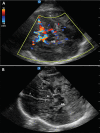

Point-of-care Cranial Ultrasound in a Hemicraniectomy Patient